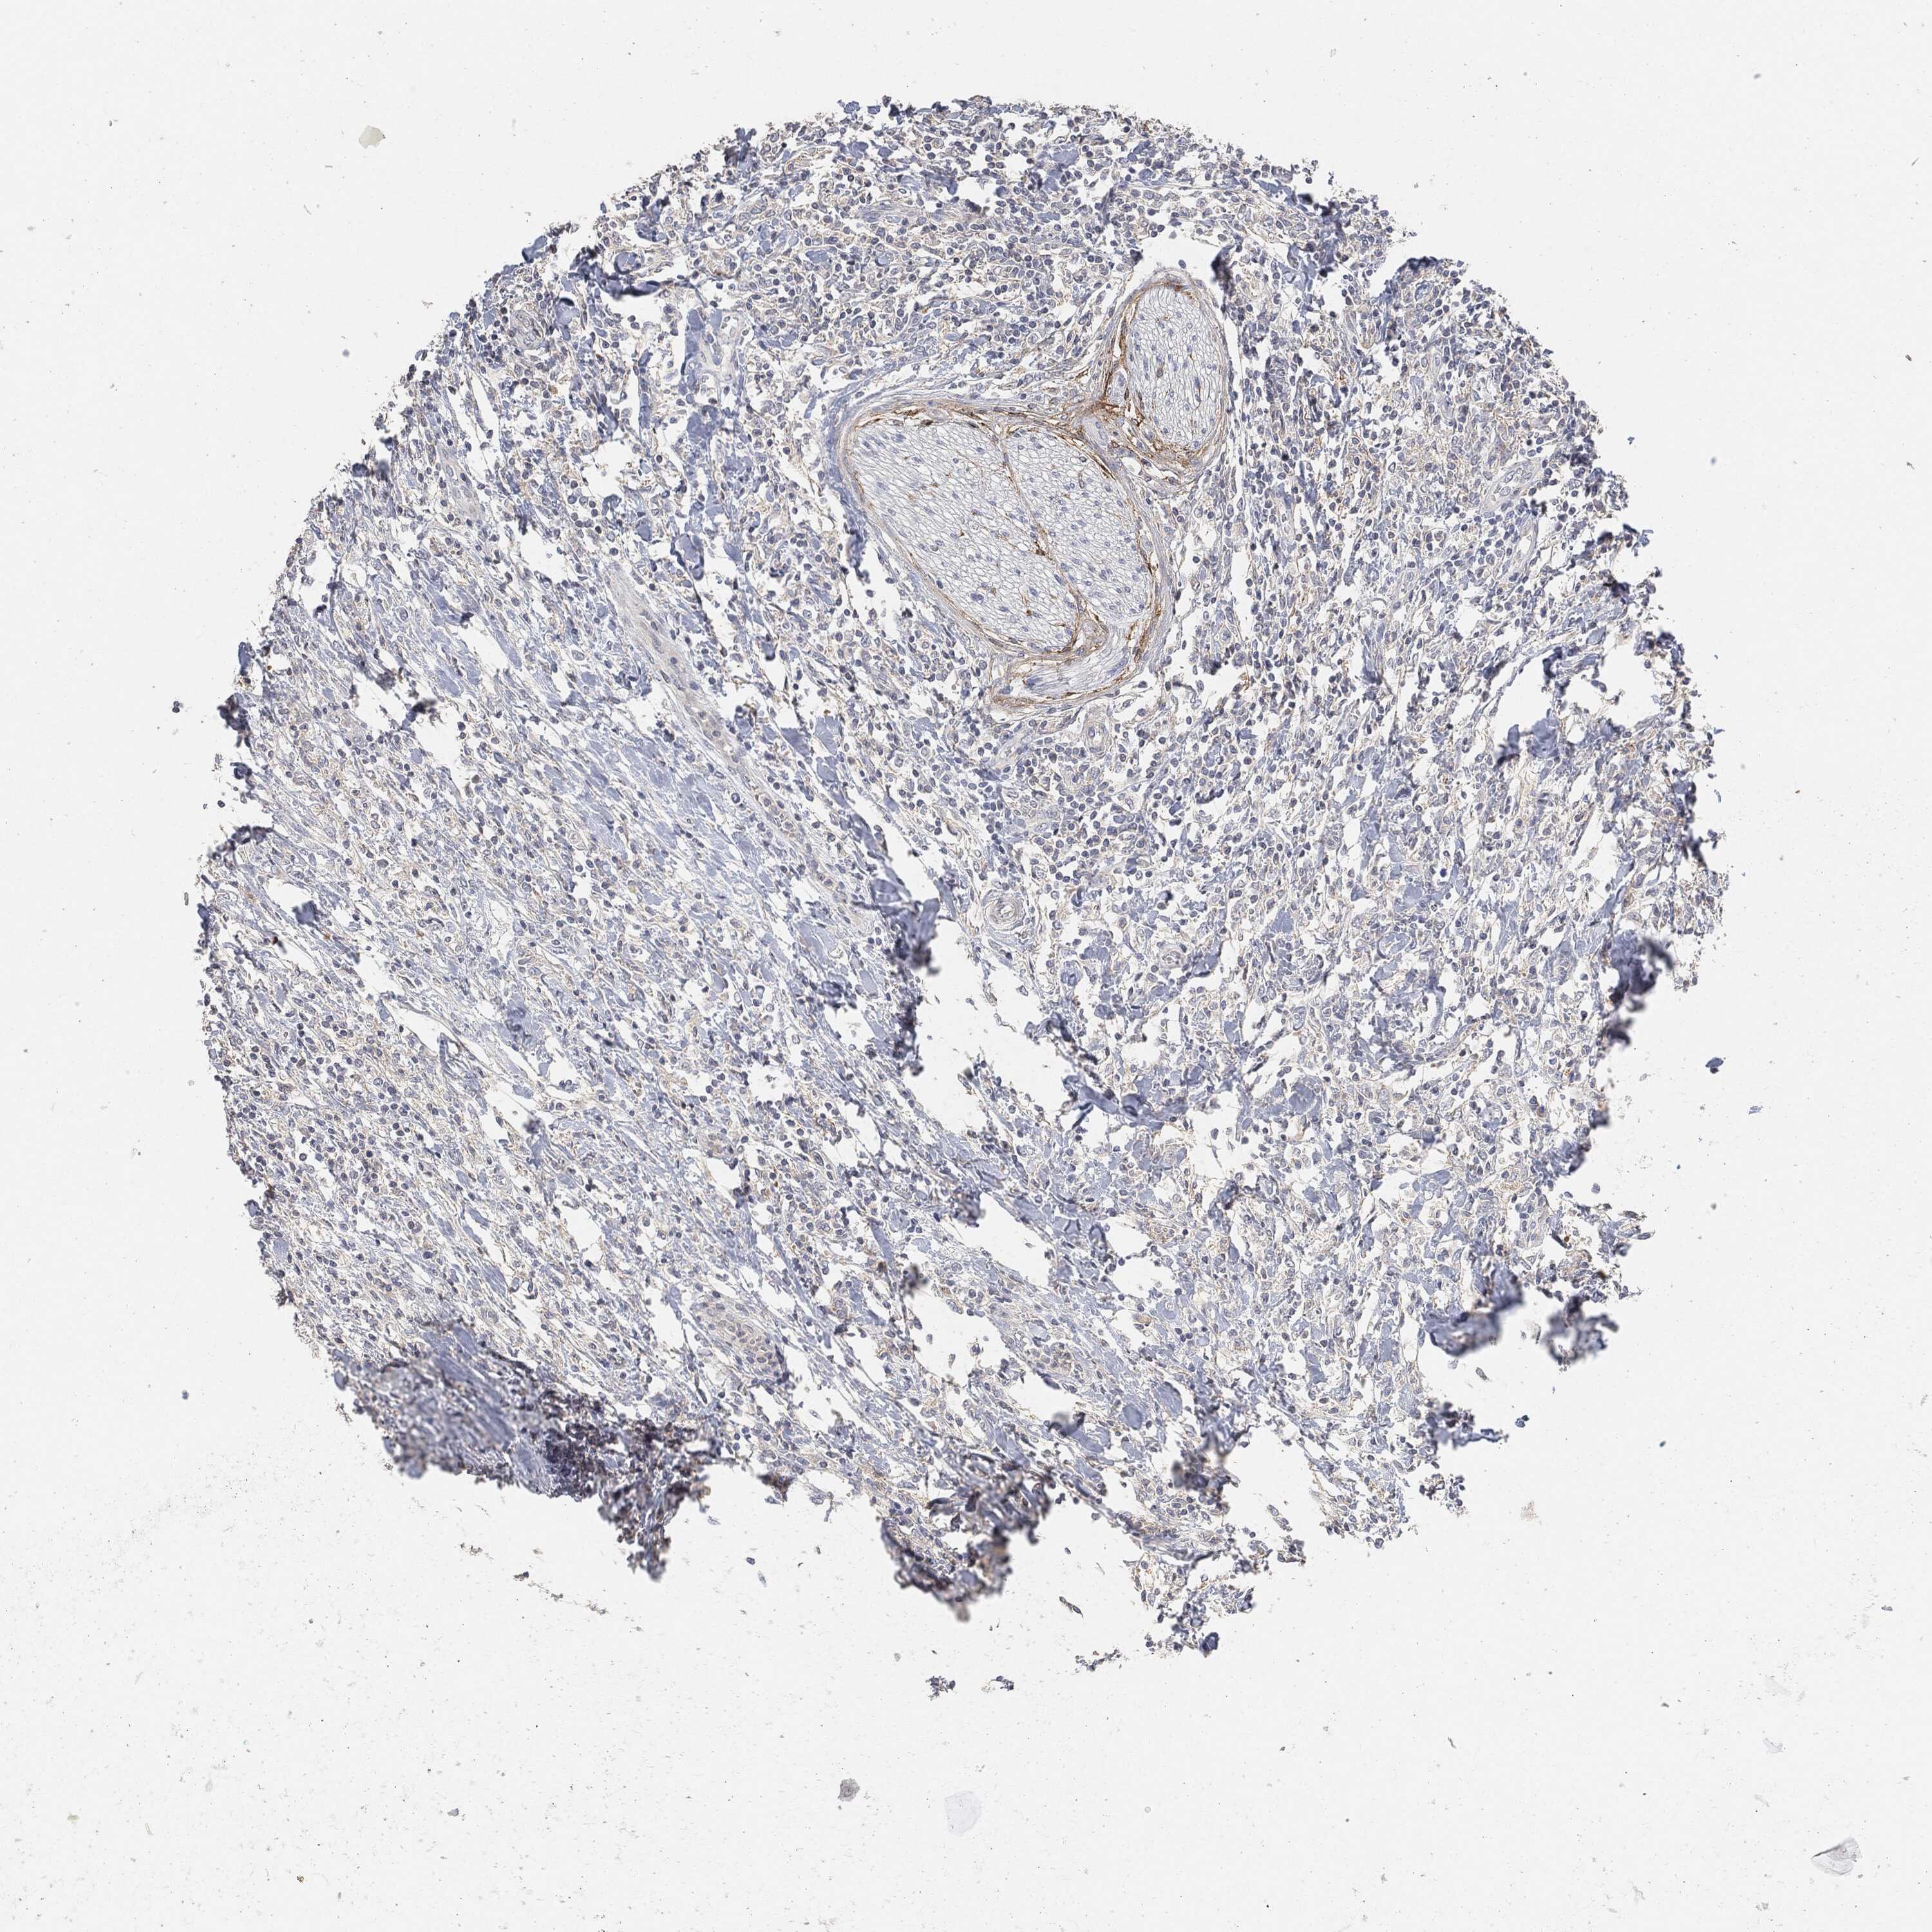

CANCER LYMPHOMA Show tissue menu

LYMPHOMA - Protein expressioni

A mouse-over function shows sample information and annotation data. Click on an image to view it in a full screen mode. Samples can be filtered based on level of antibody staining by selecting one or several of the following categories: high, medium, low and not detected. The assay and annotation is described here.

Antibody stainingi

Antibody staining in the annotated cell types in the current human tissue is reported as not detected, low, medium, or high, based on conventional immunohistochemistry profiling in selected tissues. This score is based on the combination of the staining intensity and fraction of stained cells.

Each image is clickable and will lead to virtual microscopy that enables deeper exploration of all samples and also displays staining intensity scores, fraction scores and subcellular localization as well as patient and tissue information for each sample.

Malignant lymphoma, non-Hodgkin's type, High grade

Hodgkin's disease, NOS

Malignant lymphoma, non-Hodgkin's type, Low grade